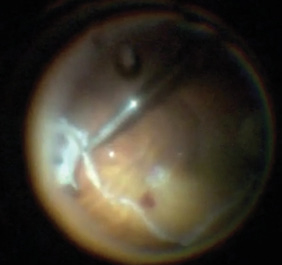

Figure 2. Creating a 180-degree inferior relaxing retinotomy using the vitreous cutter after demarcation with diathermy.

Perfluorocarbon liquid (PFCL) (Perfluoron, Alcon) was used to flatten and stabilize the posterior retina. The surgeon used bimanual technique with a 23-gauge lighted retinal pick (Alcon) and MaxGrip forceps (Alcon) to peel preretinal membranes completely off the retinal surface. All retinal breaks were identified. After maximal membrane peeling, intraretinal contraction was observed. Therefore, a 180-degree inferior relaxing retinotomy was outlined with diathermy then completed using the vitreous cutter (Figure 2). The anterior retinal tissue was removed, and the retina relaxed nicely under PFCL.